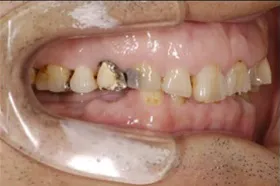

インプラント治療及び補綴治療のケース

■治療前:奥歯が無いため噛み合わせが深く下の歯が全く見えない

噛み合わせが低いため全体的に歯が削れている

■治療後:下顎 左下5・6番、右下4・6番にインプラント治療

その他の歯に補綴治療をしたことにより、奥歯もしっかりと咬むことができ、奥歯ができたことにより噛み合わせも上がって下の歯も見えるようになり、審美的にも改善された

| 主訴 | 歯科治療をしても歯がすぐに欠けてしまう 奥歯が無いため、奥歯で咬めない |

| 治療方法 | インプラント治療 + 補綴治療 |

| 治療期間 | 約1年 |

| 通院回数等 | 約20回 |

| 費用 | 約250万円(税込) |

| リスク・副作用 | 術後の腫れ・痛み |